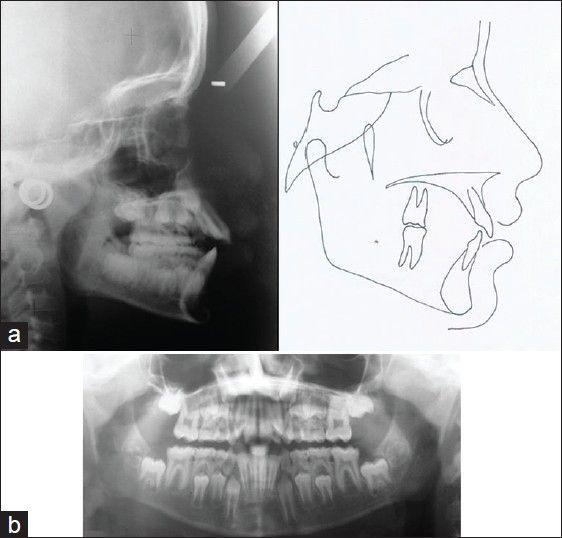

Digit sucking habit is a learned pattern of behavior commonly seen in children of preschool age. Prolonged digit sucking beyond the preschool age, lead to the development of malocclusion such as anterior open bite, maxillary constriction and posterior crossbite. Treatment strategies include interception of habit and correction of the malocclusion. The present case report describes a modified quad helix appliance used successfully in a 9-year-old child to intercept thumb sucking habit and simultaneous correction of posterior crossbite. The appliance has the advantage of easy fabrication, being versatile and more patients compliant.

吮指习惯是一种常见于学龄前儿童的习得性行为模式。超过学龄前年龄仍长期吮指会导致错颌畸形的发展,如前牙开颌、上颌缩窄和后牙反颌。治疗策略包括戒除习惯和矫正错颌畸形。本病例报告描述了一种改良的四螺旋矫治器,成功用于一名9岁儿童,以戒除吮拇习惯并同时矫正后牙反颌。该矫治器具有制作简便、用途广泛且患者依从性更高的优点。